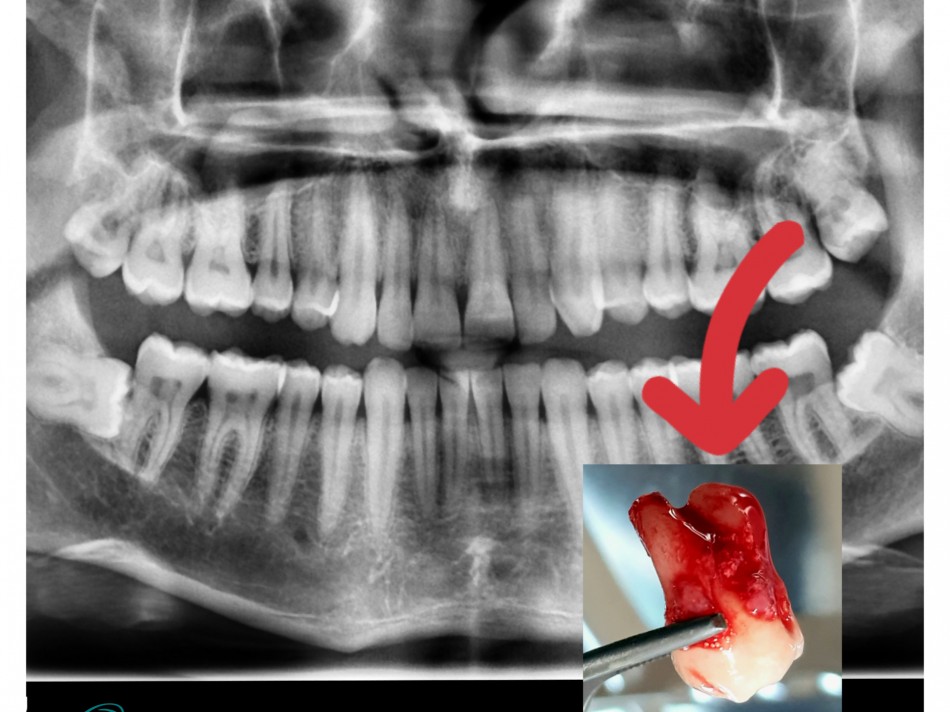

Tooth Extractions

Careful & Painless Removal of hopeless tooth by experienced Dental Surgeons.